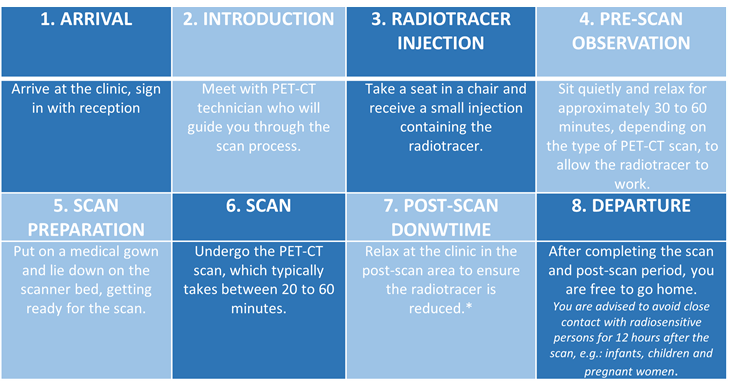

What does the procedure involve?

What happens next?

The report will be shared with your Oncologist within one to three days. They will then discuss the results with you.